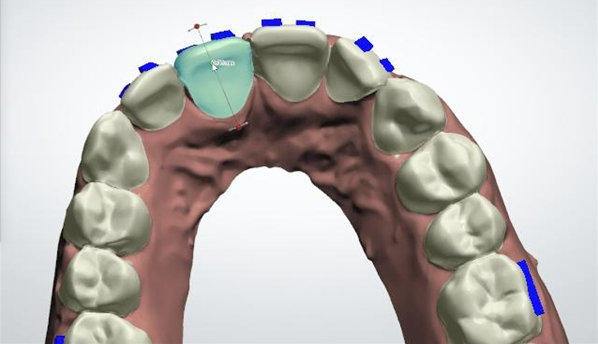

作为首家互联网口腔专科医院平台,平台集中各方力量及资源,聚焦于隐形正畸这一细分医疗领域,目前国内隐形矫正市场还是将主要关注度集中在隐形牙套的产品上,基于这一现状,微笑工场将平台的核心竞争力聚焦于引进国际和国内超一线专家团队与平台内隐形正畸配套的医疗服务AI技术的研发,主要是解决中国中小型口腔机构正畸专家的稀缺与运营能力不足的两大短板。

微笑工场平台为中国上万家中小型口腔门店赋能,最核心的就是平台上的国际和国内正畸专家团队的赋能,平台专家团队来自国内头部一线正畸专家、院长以及博士,目前平台专家团队在紫丁香口腔医院张良琼院长以及北京口腔医院正畸科主任张宁博士的带领下,已经具有几十名专家的团队规模,平台以严谨并开放的态度,带动着更多的正畸专家入驻进来,为全国中小口腔机构的隐形正畸项目贡献专业力量,目前平台已覆盖全国380座城市,结合平台AI远程技术实现全国7*18小时远程医疗服务。

平台专家对提交的病例进行专业的方案设计与把关,同时合作门诊的医师可全程跟踪学习;